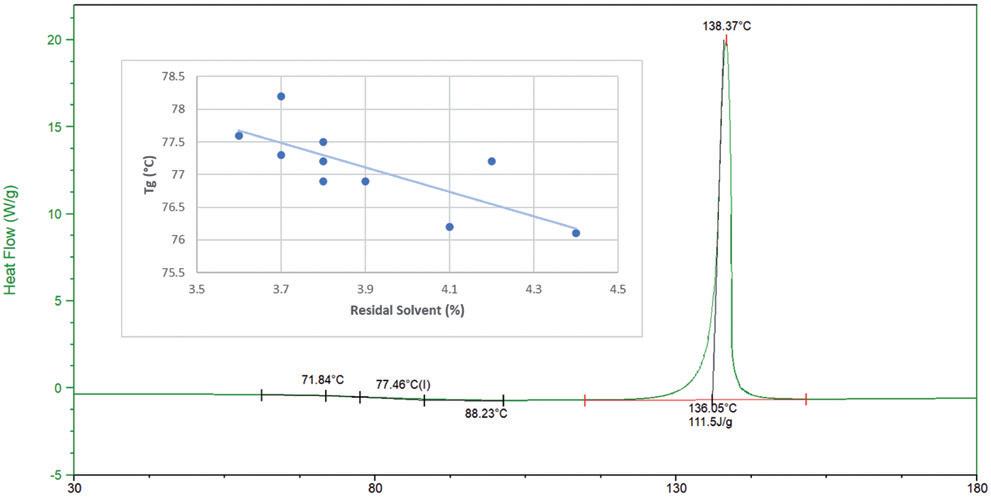

High-Dose Delivery Platform for Crystalline DPIs

Susana Saldanha, R&D Manager – Inhalation and Advanced Drug Delivery; Lídia Santos, Analytical Scientist – R&D ; and Rui Churro, Senior Scientist – Inhalation and Advanced Drug Delivery

Hovione